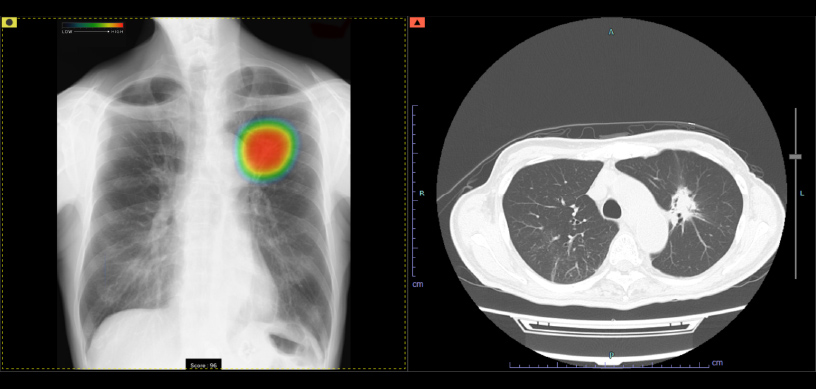

ヒートマップ表示機能

異常が疑われる領域をAIが自動的に解析し、確信度に合わせた表示を行います。確信度のスコアは0~100に分かれており、画像では色分けによるヒートマップとして表示されます。

スコア表示

0~100に分けられた確信度スコアの最大値が数値として表示されます。